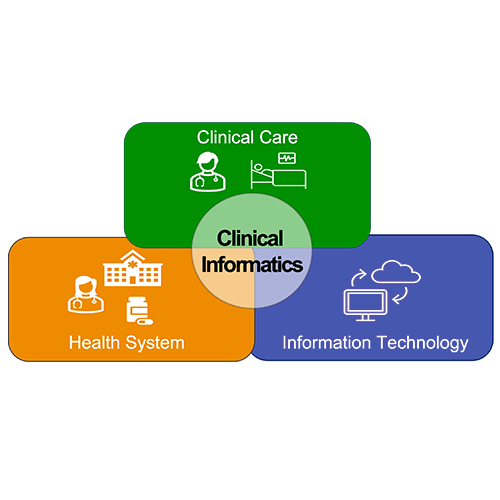

Clinical Informatics →

The mission of the Clinical Informatics Fellowship Program at UMass Chan Medical School is to train the next generation of clinical informaticists to apply information technology toward advancing and transforming patient care, enhancing patient and staff safety, and improving clinical outcomes. We will accomplish this mission by recruiting trainees with backgrounds in internal medicine and other clinical specialties who will be given rigorous training in clinical informatics, quality improvement and research methods. Educational programs and project work will align with the missions of UMass Chan and UMass Memorial Health, both of which are deeply committed to population health and to improving the health of the people in Central Massachusetts.